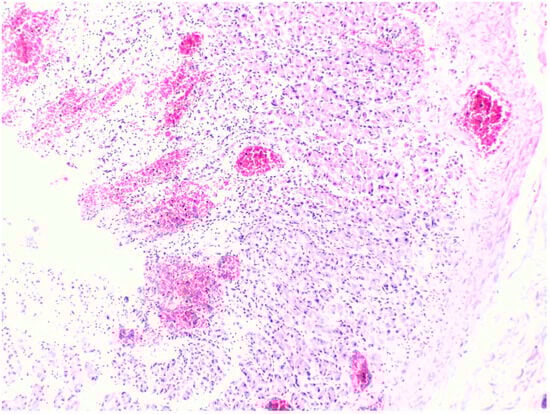

3.2. Microscopic Histopathological Findings

| Autopsy Case No. | Brain | Heart | Lung | Liver | Spleen | Kidney | Adrenal Gland | Esophagus/ Stomach |

|---|---|---|---|---|---|---|---|---|

| 1 | N/A | Hemorrhage at subendocardial and myocardium | Edema | Steatosis | N/A | Partial autolysis | Partial autolysis | N/A |

| 2 | N/A | N/A | N/A | Steatosis | N/A | N/A | N/A | N/A |

| 3 | Subarachnoid congestion, hemorrhage, eosinophilic neurons | Thrombosis, myocardial necrosis, focal subendocardial hemorrhage, atherosclerosis | Diffuse alveolar damage, fibrin platelet thrombi | Multifocal ballooning degeneration (hepatocyte), steatosis | Congestion | Acute tubular necrosis, fibrin platelet thrombi in glomeruli | Focal cortical necrosis | Mucosal infarct, hemorrhage |

| 4 | N/A | N/A | Edema, congestion, petechial hemorrhage | Steatosis | Congestion | N/A | N/A | Mucosal hemorrhage, esophagitis |

| 5 | N/A | Atherosclerosis | Diffuse alveolar damage, hemorrhage, fibrosis | Cholestasis | N/A | Acute kidney injury | N/A | N/A |

| 6 | N/A | Myocardial infarction, coronary occlusion | Edema, congestion, petechial hemorrhage | N/A | N/A | N/A | Lipid depletion | Mucosal infarct, hemorrhage |

| 7 | Red blood cells within the subarachnoid space | Cardiomegaly, hemorrhage at myocardium | Edema, congestion, | Steatosis | Congestion | N/A | Lipid depletion of cortical cells | Superficial mucosal hemorrhage |